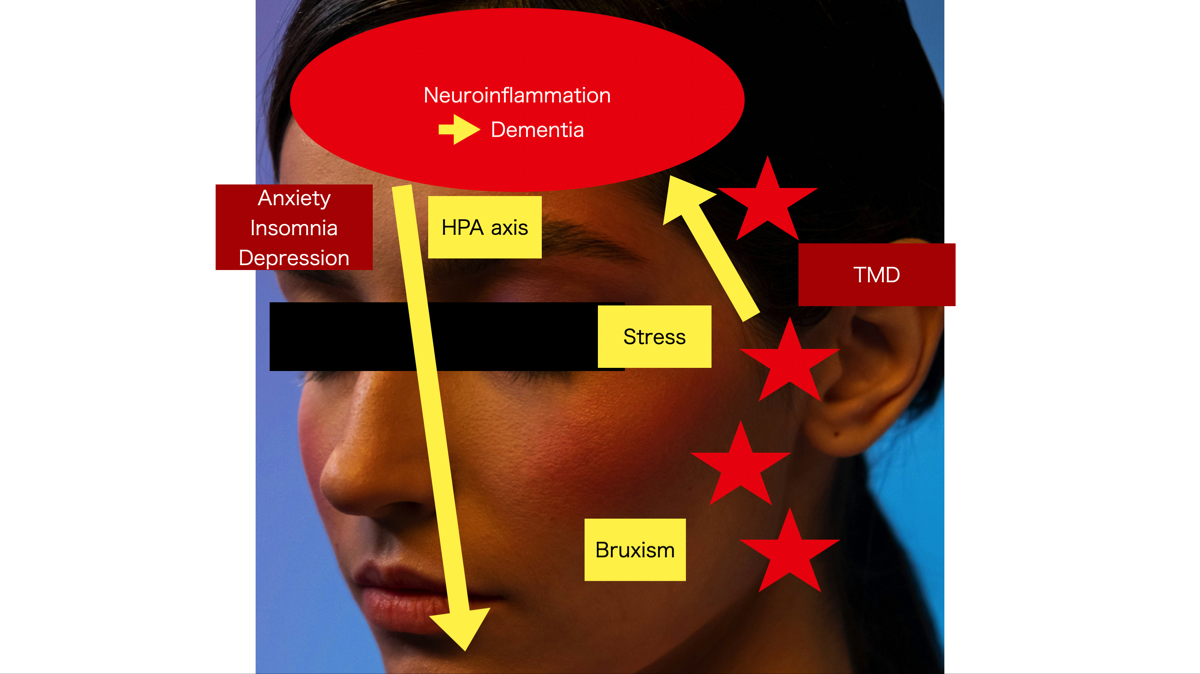

この顎関節での炎症に伴うストレスは、求心性の神経で脳に伝わり、脳でも炎症が生じます(Neuroinflammation)。

慢性的なストレスに晒された脳内では、セロトニンやアドレナリンなどの神経伝達物質のバランスが崩れ、こころのあり方にも変化をきたし、自律神経も変調して、不安(Anxiety)、不眠(Insomnia)あるいはうつ状態(Depression)が生じることがあります。内分泌系や免疫系にも影響が及ぶので体調不良ともなり得ます。

また、顎関節の後方組織内を中耳に酸素や栄養を運ぶ血管が走行していて、重症例ではその血管が潰れて見られなくなるようなので、難聴にもかかわる事になります。ストレスや難聴は、認知症の原因です。

夜中の歯ぎしりやくいしばりなど(Bruxism)は、ストレスからとも言われています。なにぶん寝てる間の出来事なので自分で気づくことはむずかしいですが、起床時のこめかみ部の痛みは夜中の歯ぎしりなどが原因と思われます。

この顎関節での炎症に伴うストレスは、求心性の神経で脳に伝わり、脳でも炎症が生じます(Neuroinflammation)。

慢性的なストレスに晒された脳内では、セロトニンやアドレナリンなどの神経伝達物質のバランスが崩れ、こころのあり方にも変化をきたし、自律神経も変調して、不安(Anxiety)、不眠(Insomnia)あるいはうつ状態(Depression)が生じることがあります。内分泌系や免疫系にも影響が及ぶので体調不良ともなり得ます。

また、顎関節の後方組織内を中耳に酸素や栄養を運ぶ血管が走行していて、重症例ではその血管が潰れて見られなくなるようなので、難聴にもかかわる事になります。ストレスや難聴は、認知症の原因です。

夜中の歯ぎしりやくいしばりなど(Bruxism)は、ストレスからとも言われています。なにぶん寝てる間の出来事なので自分で気づくことはむずかしいですが、起床時のこめかみ部の痛みは夜中の歯ぎしりなどが原因と思われます。